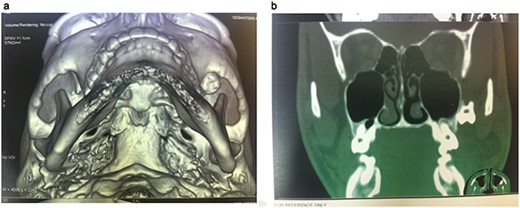

Clinical examination revealed a slight swelling of the face without signs of local infection and without restriction in mouth opening. The displaced tooth was not palpable at the soft tissue-affected area. The radiographic was examined by use of computed tomography (CT) scan with 3D reformation. CT examination demonstrated the presence of the tooth into the ipsilateral infratemporal fossa with its lowest level of masticatory surface of the crown being at the inferior border of malar bone adjacent to the coronoid process (Fig. 2a and b). A prompt surgical removal of the dislodged tooth was recommended to the patient to avoid possible post-extraction infection.

CT 3D reconstruction showing the exact location of the displaced molar into the infratemporal fossa behind the zygoma.